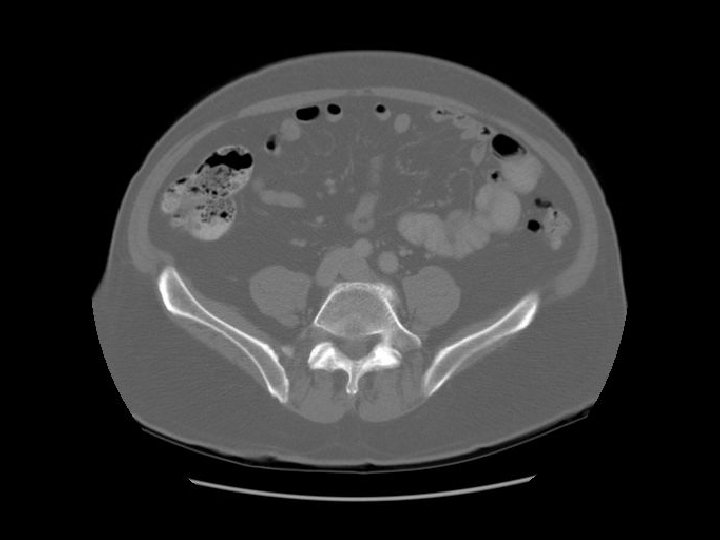

Diverticula in recto sigmoid Rectosigmoid

Arrows are pointing to air filled diverticulum and the second one is filled with residual barium from an old GI study.

Gluteus